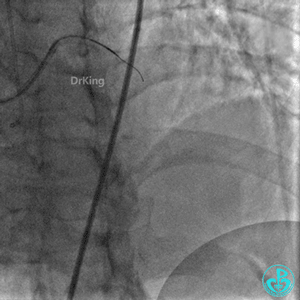

胸片及心脏超声无异常发现。

明胶在血管怎么降解并发症丨前降支CTO同侧逆向开通时侧支血管破裂,弹簧圈联合明胶海绵封堵_https://www.jmylbn.com_新闻资讯_第3张